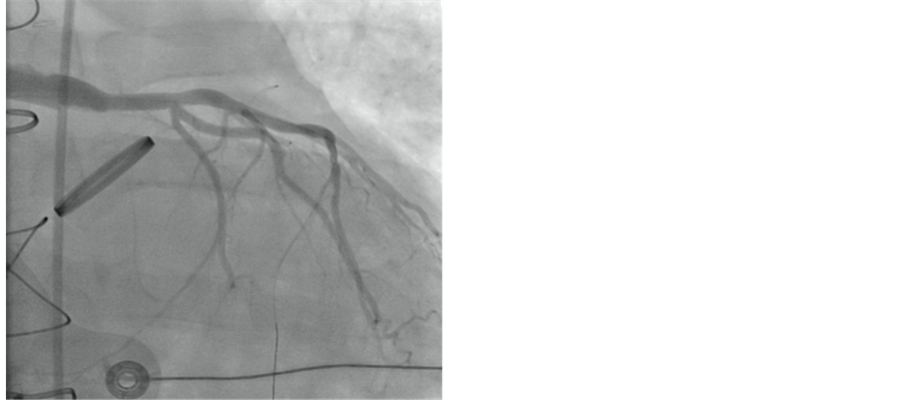

A 6 F JR4 guiding catheter 100 cm (Infiniti, Johnson and Johnson/Cordis, NJ) was used to engage the graft. A 0.014” 50 cm guide wire (Pilot, Abbott Vascular, CA) was advanced and placed distally in the native left anterior descending artery. Attempt to aspirate the thrombus with the aspiration catheter (Fetch2, Medrad Inc., PA) failed to restore any flow. Decision was made to perform mechanical thrombectomy with the 4F Angiojet catheter (Spiroflex, Medrad Inc., PA) two runs performed for 45 seconds each resulting in restoration of TIMI-3 flow (Figure 2). Repeat angiography showed that there was an anastomotic lesion of 75% in severity. A 4.0 × 15 mm bare metal stent (Vision, Abbott Vascular, CA) was deployed at 16 atms (Figure 3). A total of 1000 mcg of intracoronary adenosine was administered. ACT by HemoTech was 280 seconds and 600 mg Clopidogrel was loaded by the nasogastric tube at the end of procedure. The

Figure 3. Post-treatment RAO angiogram view after stenting of left limb of Cabraol graft with TIMI 3 flow.

patient was transferred to the tertiary hospital intensive care unit. He was discharged five days after the primary PCI. At one year follow up, the patient was symptom free.